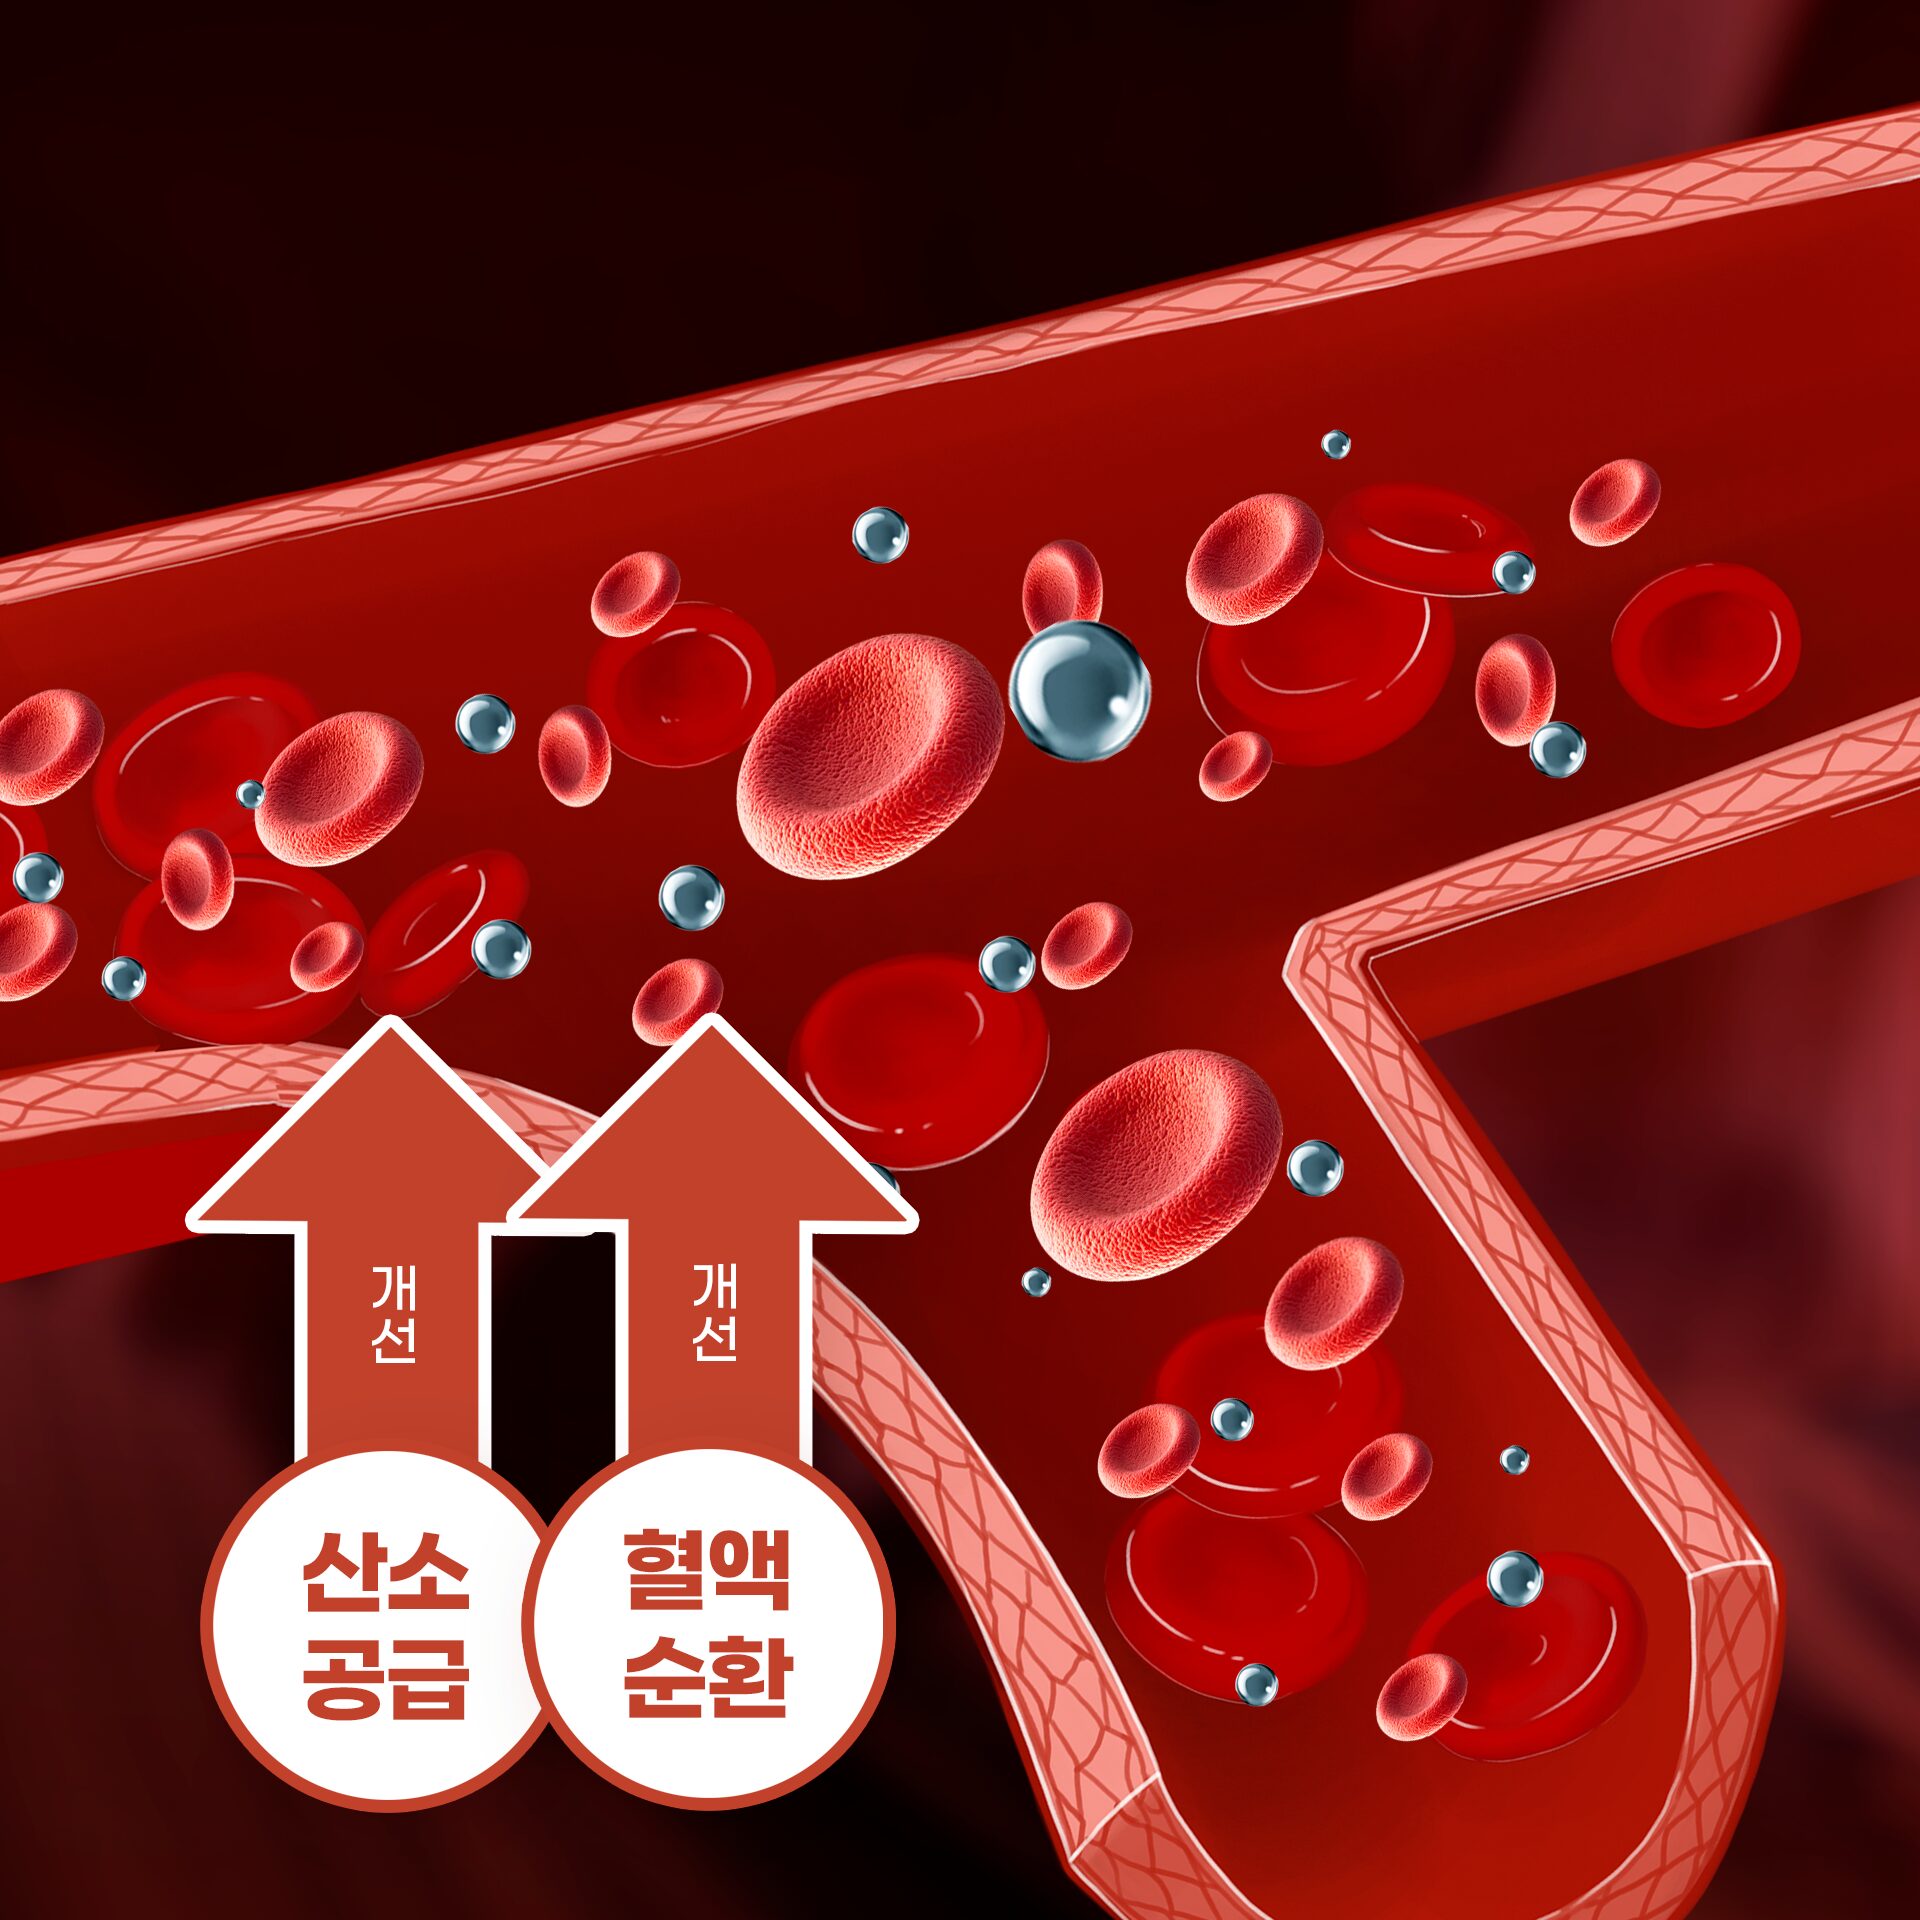

혈액 순환 개선 및 영양 공급

산소 공급이 원활해져 혈액 순환이 개선되고, 피부에 영양과 산소가 충분히 전달되어 맑은 피부 톤과 건강한 안색을 유지합니다.

산소 공급이 원활해져 혈액 순환이 개선되고, 피부에 영양과 산소가 충분히 전달되어 맑은 피부 톤과 건강한 안색을 유지합니다.

혈액순환의 활성화로 부종이나 멍 회복에 도움이 됩니다

기압을 높이면 적혈구와 결합하지 않아도 산소 분자 그대로 혈액 속으로 녹아들어 모세혈관과 세포까지 활성화되어 새로운 혈관들이 생성될 수 있는 환경을 조성합니다